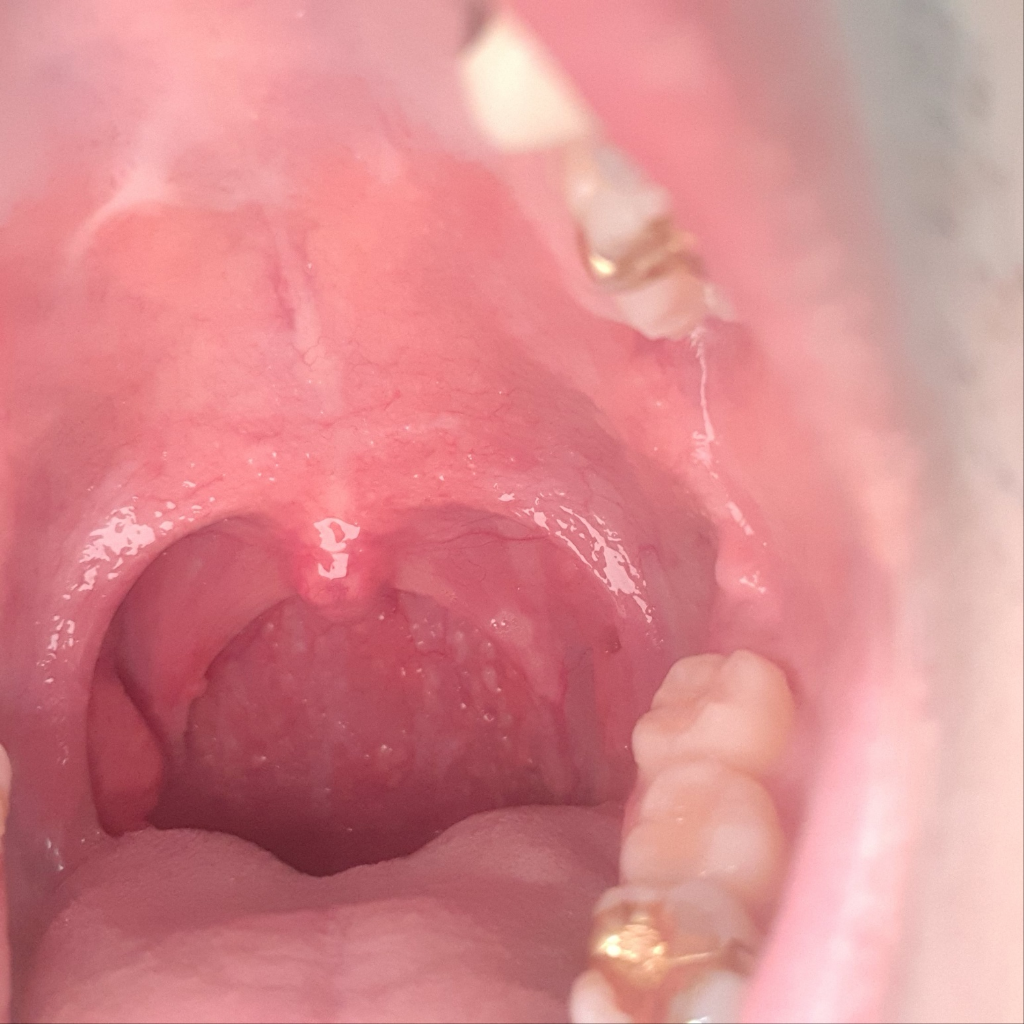

이정도면 편도가 큰건가요?제가 편도가 비대칭인데

편도가 제가 비대칭인데 한쪽이 약간 더 큰데 이비인후과에서는 아무소리도 없던데 요즘따라 더 커진 느낌인데 느낌상 이정도면 큰건가요??이거로 인해 불편한건 없습니다

• 2번 째 사진

• 사진의 소견만 놓고 정확하게 어떻다 말씀드리기는 부적절하긴 하나, 사진의 소견을 통해서 보았을 때에는 편도가 별로 크지 않습니다.

사진으로 볼 때 편도는 그리 큰 편이 아닙니다. 평균적인 수준이라고 볼 수 있겠고 걱정할만한 문제는 없어보입니다.